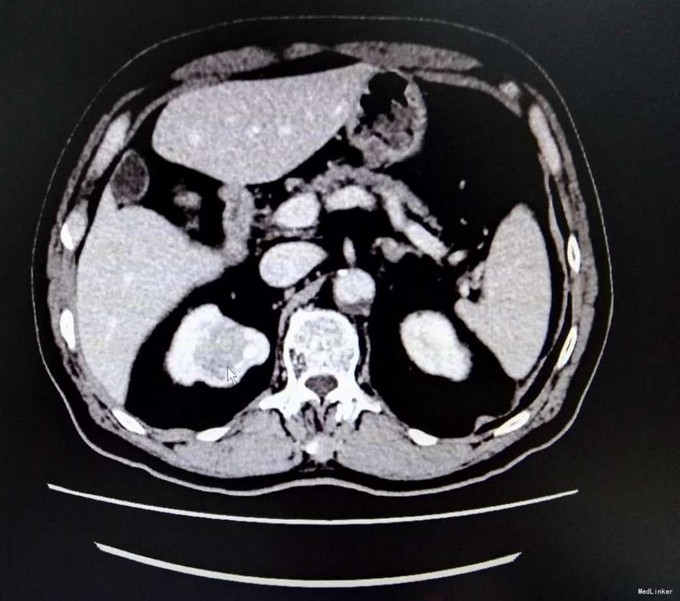

3、查体:无明显阳性体征 4、辅助检查:生化:肌酐:144umol/L。双肾CT平扫+增强:右肾上部肿块,考虑肾癌可能性大,ECT示:左肾 GFR 21.6ml/min,右肾GFR为22.3ml/min

5、肾癌 6、患者入院后完善相关检查,具体检查如上述,未见明显禁忌症,与患者及其家属充分沟通后,行腹腔镜下右侧肾癌根治术,术中未明显出血,术后患者恢复良好,术后病理提示肾透明细胞癌,患者顺利出院